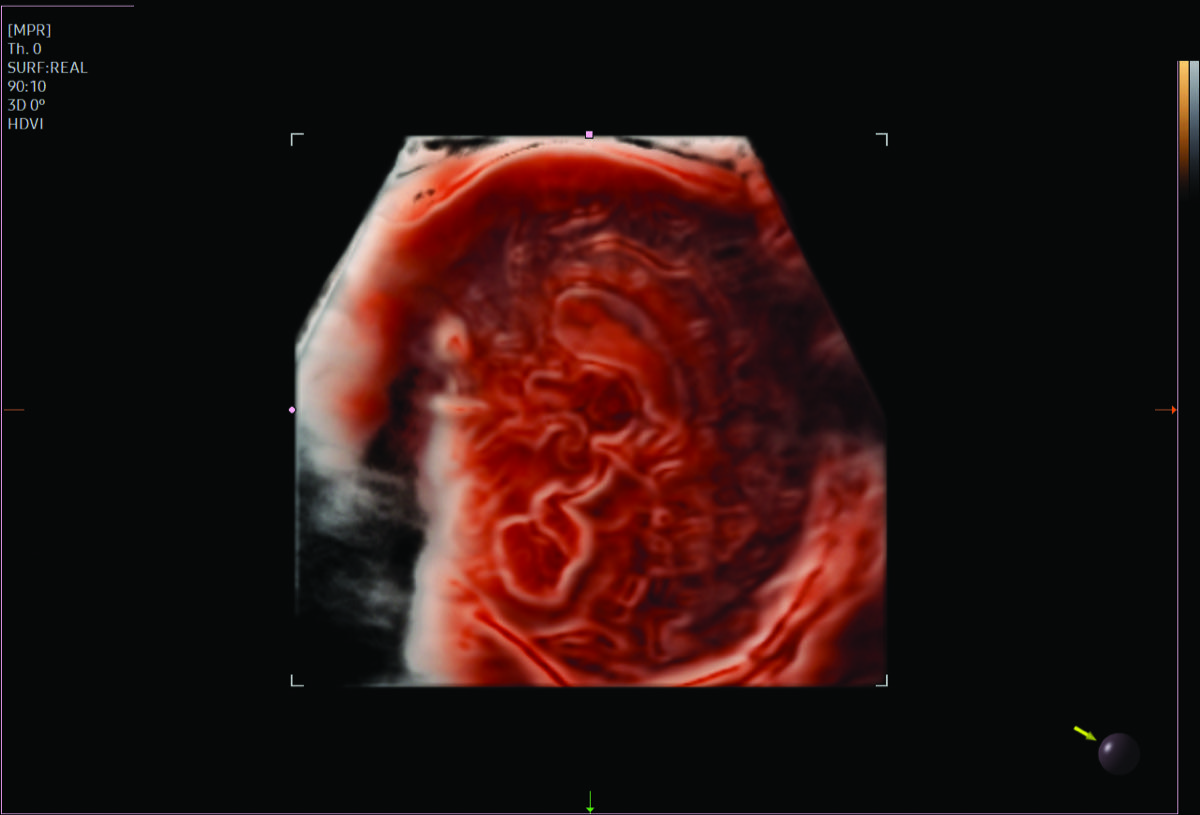

Comprehensive, advanced and expert MFM care for high-risk pregnancies

- Fetal anomalies